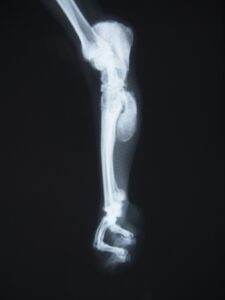

↑ この写真は、当院が骨瘤治療を開始した

『第一症例』の初診時のレントゲン像です。